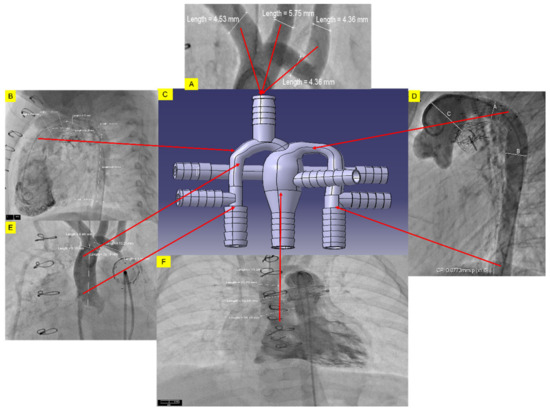

2.1.2. In-Vitro Phantom